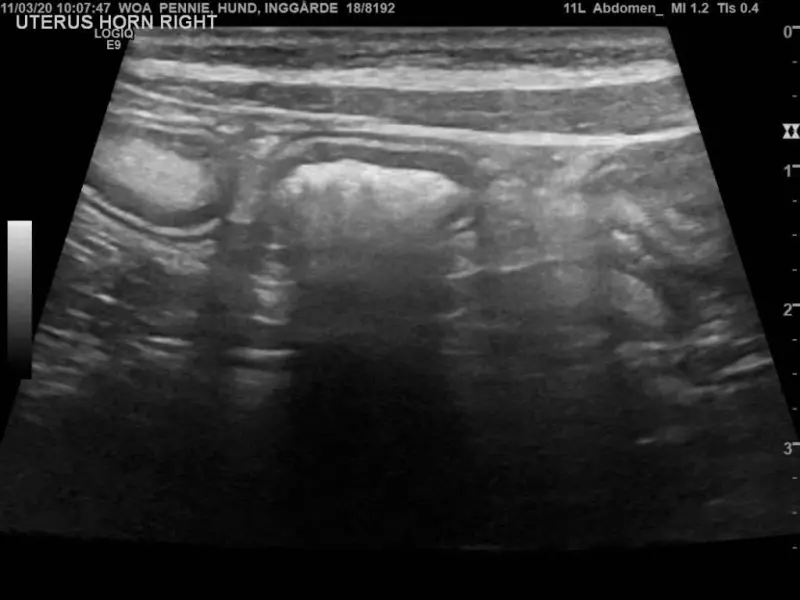

Kolejny epizod koprostazy wystąpił w 2020 r. Ponownie stwierdzono w USG obecność torbieli wypełnionej echogennym płynem, wielkości ok. 5 × 2 cm. Zastosowano identyczne leczenie jak poprzednio. Usunięto zawartość torbieli, którą określono jako ropień, torbiel przepłukano roztworem fizjologicznym. Ponownie wykonano cytologię i posiew – nie wykryto bakterii.